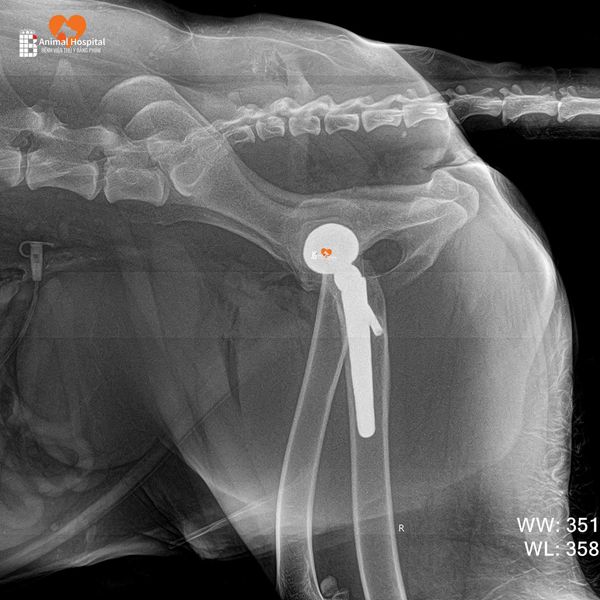

Ảnh X-quang hậu phẫu cho thấy:

- Implant được đặt đúng vị trí

- Trục khớp chuẩn xác

- Tiếp xúc xương tốt – là tiền đề lý tưởng cho sự phục hồi.